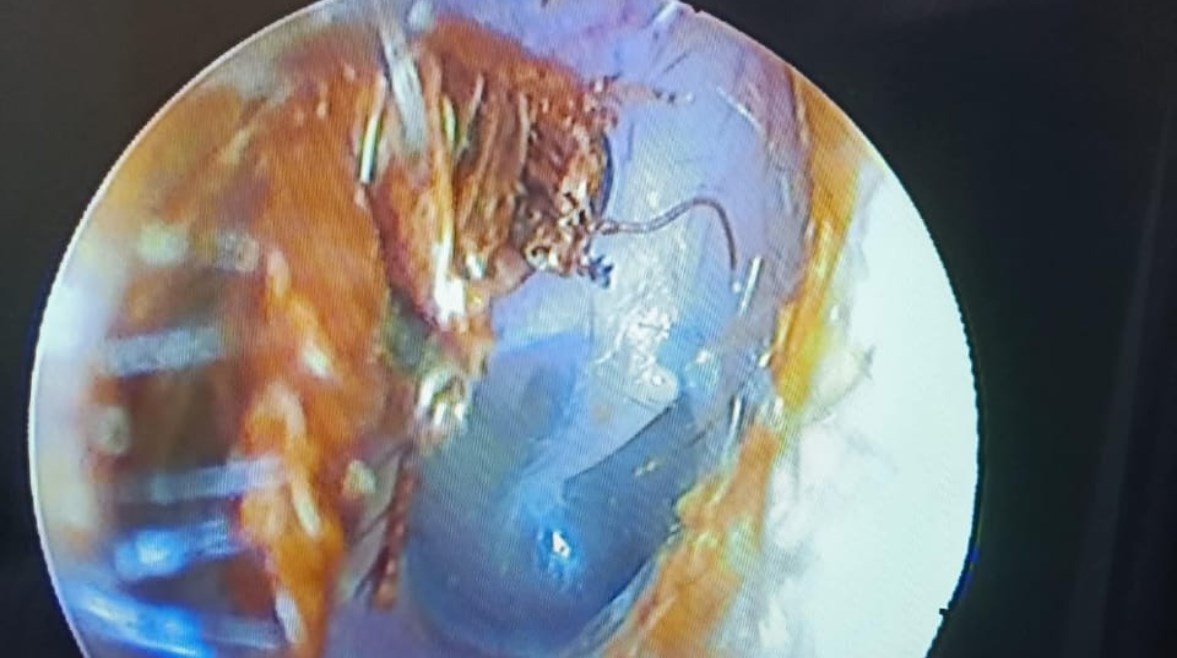

صرصور داخل أذن المريض

حكى نصر، في منشوره عن تفاصيل حالة الشاب التي عالجها حيث قال: "حالة اليوم لشاب كان قاعد في كافيه، فجأة حس بألم في أذنه، افتكره التهاب وهيروح لوحده جاء لي بعد يومين لقيت المنظر ده، صرصور بالأذن".

وتابع: "مشكلة الصرصور إنه لما بيدخل الأذن إنه مش بيعرف يرجع بظهره فيمشي داخل الأذن الخارجية، في اتجاه الطبلة وممكن يخرمها".